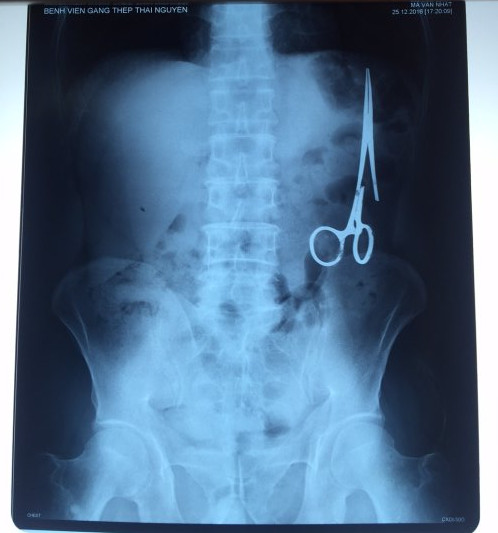

遺留在病人腹中的剪刀

據越南青年報1月2日報道,在越南首都河內醫療專家的幫助下,越南東北部的太原省(Thai Nguyen)鑄鋼醫院的醫生日前從54歲患者M.V.N腹中取出一把醫用剪刀。這把剪刀是此前曾為M.V.N手術的醫生遺留的,已經在其腹中待了18年時間。

醫務人員表示,這把剪刀遺留在病人腹部左側,與結腸緊挨著。剪刀的把手已經生銹,部分器官也已經與剪刀粘連起來。但在過去多年中,M.V.N沒有任何不適感覺,也從未因為留在腹中的剪刀引發的相關問題去看過醫生。直到2016年12月,M.V.N因為遭遇了一場車禍,才到鑄鋼醫院進行身體檢查。

超聲波檢查顯示,M.V.N的腸子中有個奇怪物體,看起來就像醫用剪刀。M.V.N證實,他曾于1998年6月份在北江省綜合醫院接受手術,在此后也從未進行過任何手術。近來,他感到腹部有些疼痛,并試圖通過服用藥物治療。12月27日,M.V.N回到北江省綜合醫院再次進行超聲波檢查,顯示其腹部的確存在怪異物體。

越南衛生部要求北江省綜合醫院對此事進行調查,查找當年為M.V.N做手術的醫務人員,并呈報調查結果。但北江省綜合醫院表示,醫院只會保存病人的醫療記錄15年。因此,很難確定當年到底是誰為M.V.N實施手術,更難查證責任人。